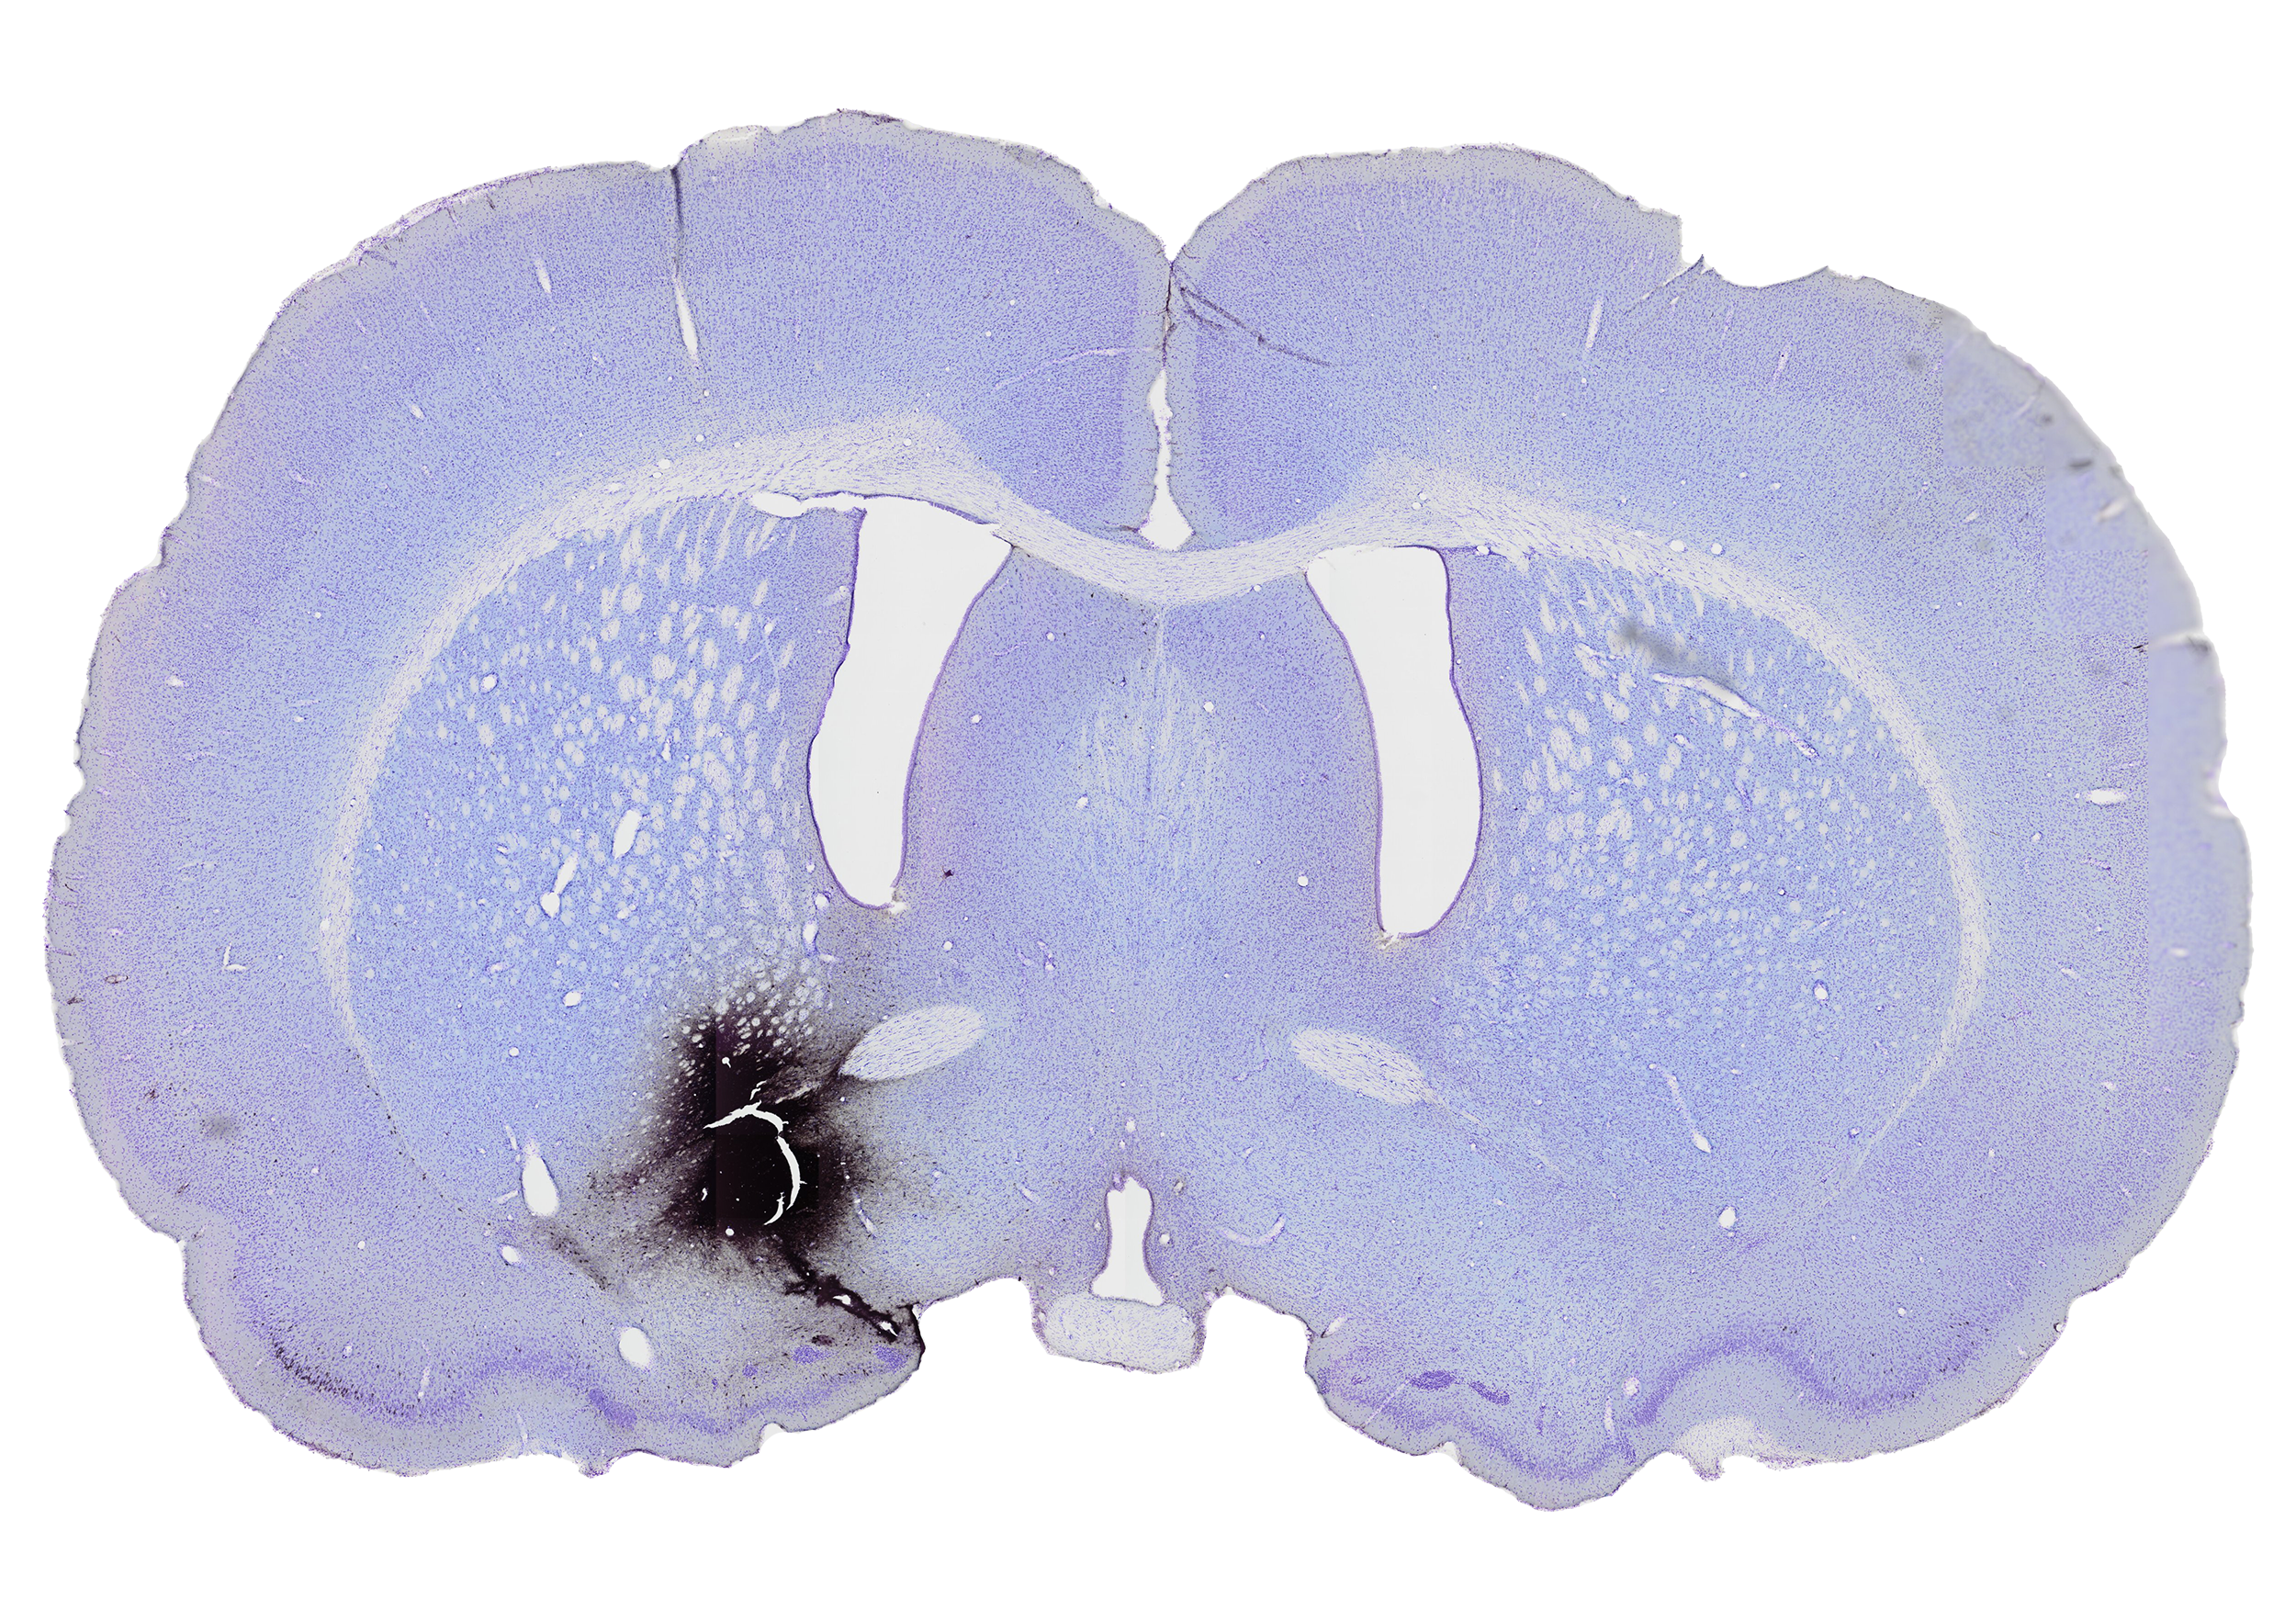

The nucleus accumbens (Acb) is a brain structure that is a central part of the limbic system. It receives input from the hippocampus, amygdala, thalamic nuclei and the medial prefrontal cortex,1 This information is being integrated in the Acb and encodes the prediction of the reward and probability of a behavioral response.2 The output of the Acb is sent to several motor systems, such as the pallidum and the hypothalamic nuclei.3, 4

In 1990 Henk Berendse et al. performed a tracing study to analyze what brain structures project to the Acb.5 This was done by injecting the retrograde tracer CTB (cholera toxine subunit B) into the Acb. This tracer makes it possible to visualize the brain structures that project to the Acb by staining the cell bodies in the brain that project to the injection site. On the figure on the left you can see the injection site into the Acb.

Nucleus Accumbens injection side